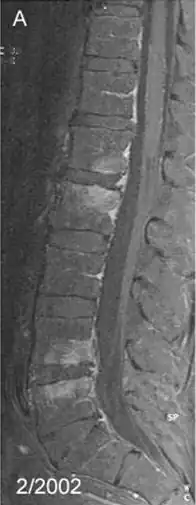

| Spondylitis due to Tropheryma whipplei: Contrast-enhanced, T1 weighted fat suppressed magnetic resonance imaging demonstrating contrast enhancing lesions of spondylitis in the first (L1) and second (L2), as well as fourth (L4) and fifth (L5) lumbar vertebra, sparing the intervertebral discs | |